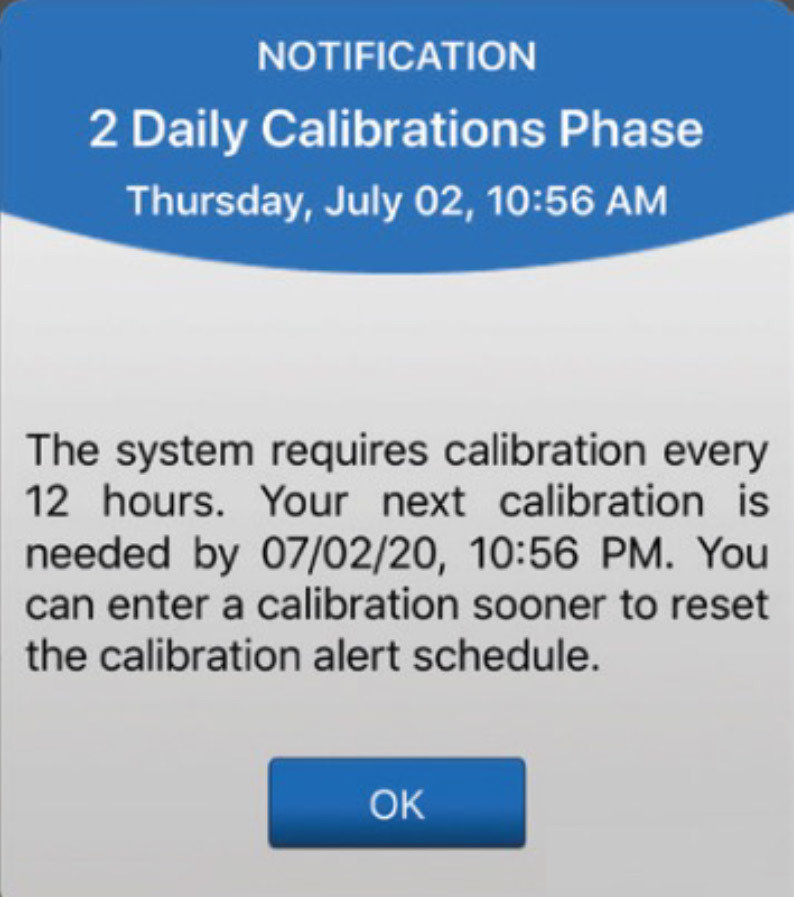

Aquí mostramos cómo funcionan juntas las alertas y notificaciones de calibración.

Cuando reciba la alerta Calibrar ahora y responda introduciendo

el valor de glucosa en sangre mediante punción capilar, recibirá una de estas dos notificaciones

si hay una actualización en

el momento de la próxima calibración.

ALERTAS Y NOTIFICACIONES DE CALIBRACIÓN

Si recibe la notificación “Fase de 2 calibraciones diarias”, significa que hay que realizar 2 calibraciones al día. Y se le recordará que realice una calibración aproximadamente cada 12 horas.

ALERTAS Y NOTIFICACIONES DE CALIBRACIÓN